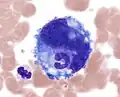

-

Emperipolesis: a band neutrophil inside a megakaryocyte (Wright-Giemsa, 100x, oil).

Emperipolesis: a band neutrophil inside a megakaryocyte (Wright-Giemsa, 100x, oil). -